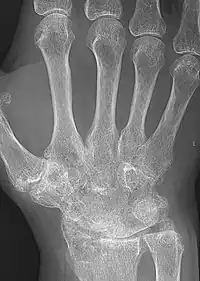

X-rays of the hands and feet are generally performed when many joints affected. In RA, there may be no changes in the early stages of the disease or the x-ray may show osteopenia near the joint, soft tissue swelling, and a smaller than normal joint space. As the disease advances, there may be bony erosions and subluxation. Other medical imaging techniques such as magnetic resonance imaging (MRI) and ultrasound are also used in RA.[20][79]